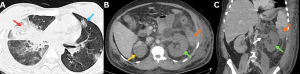

Fig 14: Case 1 -

Clinical history:

A 45-year-old patient with poorly controlled diabetes mellitus presented with fever, cough, and pleuritic chest pain.

Figure A:

Erect AP chest radiograph demonstrates multiple inhomogeneous air-space opacities in the bilateral lung fields (green arrows).

Figures B and C:

Coronal and axial HRCT images demonstrate multiple lesions with central ground-glass attenuation surrounded by a peripheral rim of consolidation in both lungs (red arrows), consistent with the reverse halo sign.

.......Case 2 -

A 50-year-old immunocompromised male presented with acute febrile illness and hemoptysis.

Figures D and E:

Axial and coronal HRCT images demonstrate multifocal areas of consolidation with surrounding peripheral ground-glass attenuation (orange arrows), representing the halo sign. Additional ill-defined ground-glass opacities are noted in the bilateral lung fields (blue arrows).